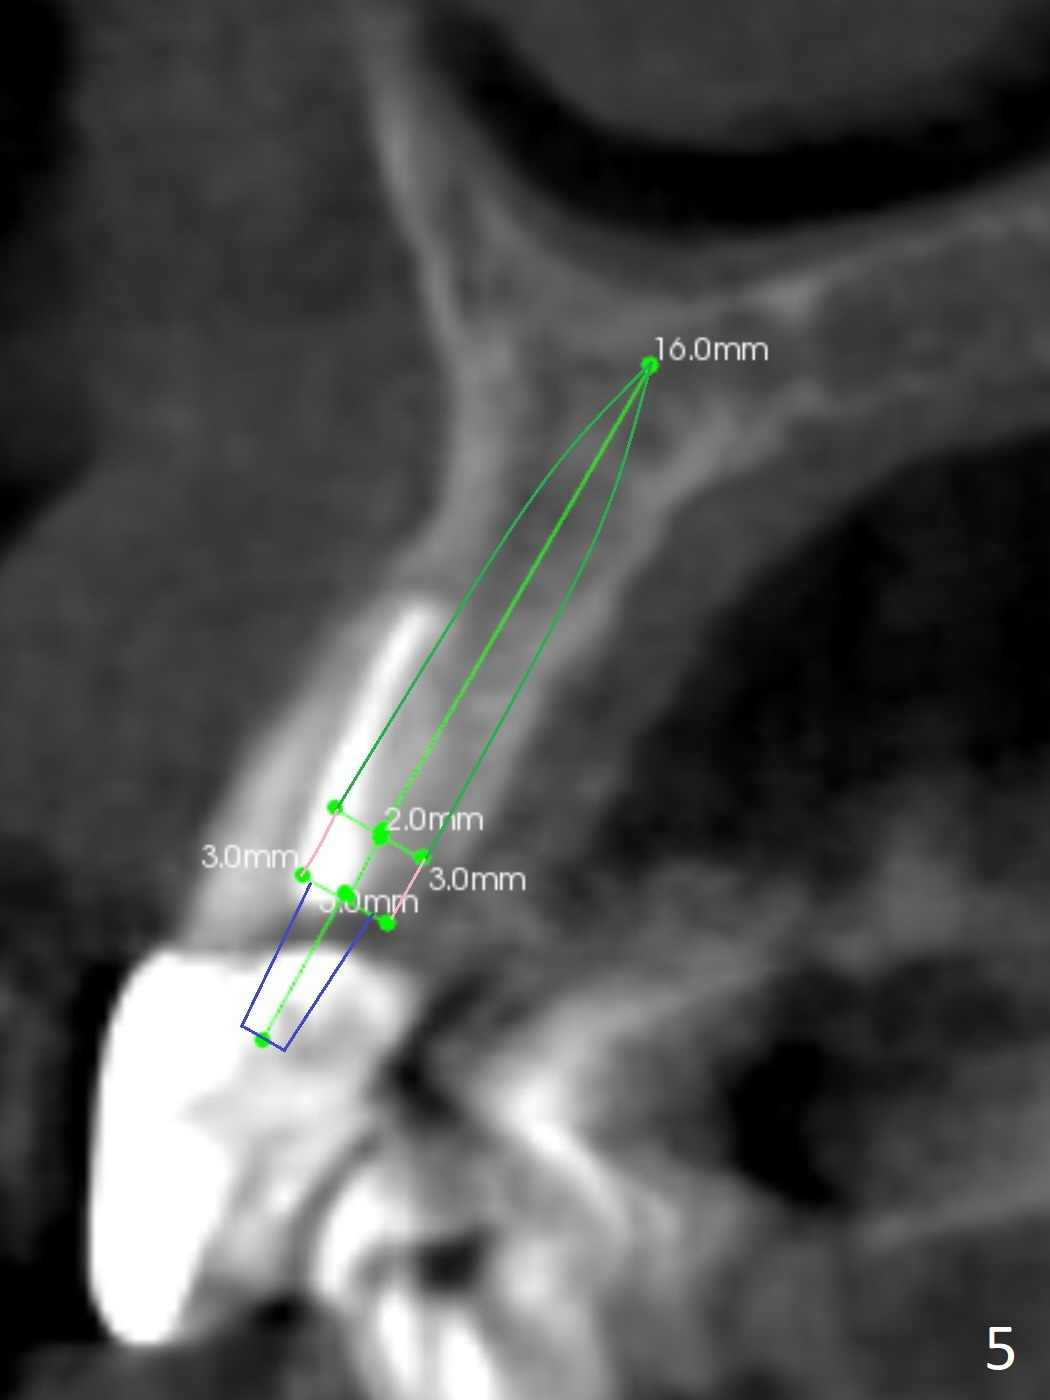

A 60-year-old man fractures the tooth #10 after implant at #7 (Fig.1). An implant should be placed in the middle of the socket at #10 since there is periapical radiolucencey at #9 and 11 (Fig.2 CBCT). The buccal plate at #10 is thin (Fig.4). A 3.8x15 mm implant (the smallest 2-piece) appears to be large for the alveolus (Fig.5). The gingiva must be thin as well. This is called thin biotype. In fact the buccal plate seems to have undergone bone resorption post 3.8x15 mm implant placement at #7. Therefore a 2.5 or 3x14 or 16 mm 1-piece implant will be placed at #10 (Fig.5). Also prepare angled ones. Take photos of #7 and 10 to show bone resorption and the thin gingiva. If the caries is not extensive, perform socket shield. In fact a 1-piece implant is chosen because of the narrow mesiodistal space.